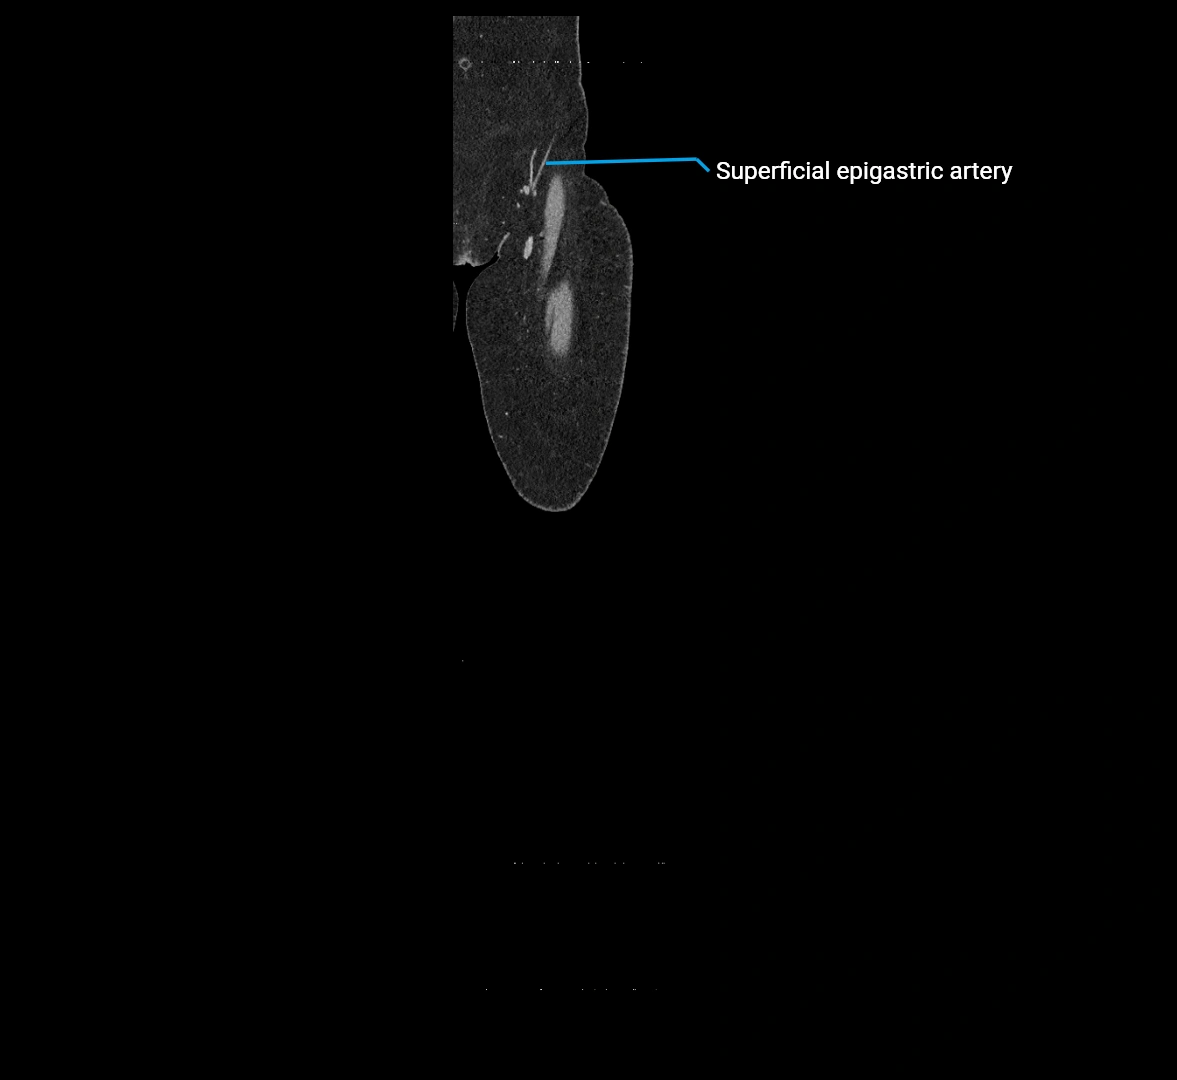

CT Appearance

Non-contrast CT:

• Appears as a tubular soft tissue structure anterior to vertebral bodies

• Calcified atherosclerotic plaques appear as hyperdense foci along the wall

• Useful for screening abdominal aortic aneurysm (AAA) size and mural calcification

Contrast-enhanced CT (CTA):

• Gold standard for abdominal aortic imaging

• Provides excellent detail of lumen, wall, aneurysm, thrombus, and branch vessels

• Multiplanar and 3D reconstructions help in aneurysm measurement, stent graft planning, and dissection evaluation

• Detects acute rupture, traumatic injury, or occlusion with high sensitivity